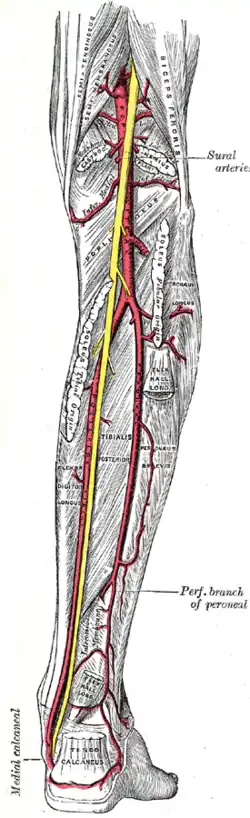

Cross-section through middle of leg The popliteal, posterior tibial, and fibular arteries

The popliteal, posterior tibial, and fibular arteries Deep nerves of the front of the leg